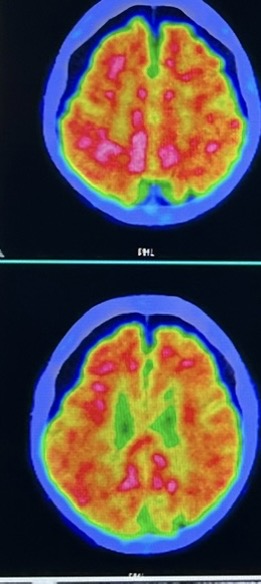

PET CT 로 본 아밀로이드

필자의 부모님의 경우  PET CT를 통해 뇌에 쌓인 아밀로이드를 측정하여 알츠하이머진단을 받았습니다.

위 사진대로 음성과 양성의 PET CT 촬영 양상을 보실 수 있으며 양성인 경우가 알츠하이머에 해당된다고 합니다.

부모님의 PET CT 입니다. 붉은 부분이 좁지 않고 넓게 퍼져있는 것이 보입니다. 가운데 부분은 음성에서도 붉은 것을 확인하실 수 있는데요, 알츠하이머는 뇌피질 즉 가장 바깥쪽에 가까운 부분까지 빨간경우 알츠하이머에 해당된다고 한다고 합니다.